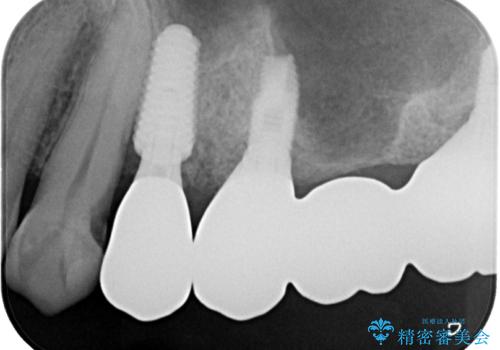

術後にインプラントの安定値を測定し、十分な値が達成された後、速やかにセラミッククラウンにて補綴治療を行うこととしました。

強い咬合力により歯根破折を繰り返しているため、即日荷重あるいは早期荷重による他の歯への負担を軽減することが重要となります。

抜歯即時埋入インプラントは、咬合力によるトラブルを回避する、非常に有用な手段となります。